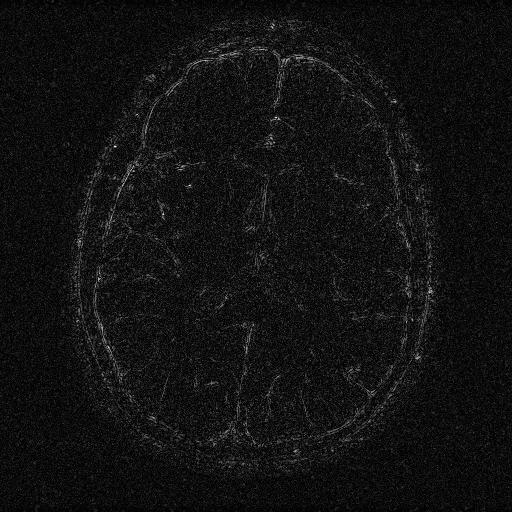

6.3. MR Image reconstruction

The second imaging application is concerned with medical imaging. Following the ideas from [32, 34], we simulate a multi-channel MRI sensing set-up, first using the same sine waves as in the previous experiment (results displayed in Fig 10), and then using spherical beam pattern (see in Fig. 11 for the results). We generate the classical Shep-Logan phantom, and set its dimension to .

The first experiment, depicted in Fig. 10 shows the results obtained by our method when using a Daubechies 4 sparsifying dictionary. Our results are compared to the single sensor analysis, and the results obtained by the Sum-of-Squares recovery [34, 32].

The recovery is obtained from noisy measurements, in which some additive Gaussian noise with variance has been added. The measurements are obtained by subsampling ( samples) of the Fourier transform. We see here that the fused compressed sensing is better capable of handling a multi-channel problem with unusual illumination (compared to the Sum-of-Squares method). Moreover, more details are preserved, when compared to the single sensor analysis method.

Some noise still appears in the image, but can easily be thresholded further if needed. One important aspect of MR Images that hasn’t been considered in this research, is the fact that they are sparse in gradient. One usually prefers to minimize the Total Variation instead of the norm or another frame using analysis.

Although we have not explicitly written the theory here, the recovered images in Fig. 11 show the results when using a TV minimization instead of the analysis.

The results were obtained from a spherical beam illuminating the input image. The measurements are obtained by sampling ( samples) of the Fourier coefficients at random iid from a Gaussian distribution. Again, some Gaussian noise with variance is added to every measurements.